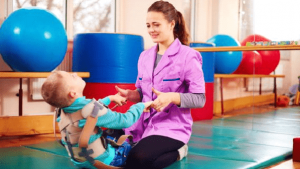

- درمان توانبخشی( فیزیوتراپی و کاردرمانی)

فیزیوتراپی

مداخله فیزیوتراپی در سه مرحله صورت می گیرد:

⦁ فاز حاد

⦁ فاز ریکاوری

⦁ به صورت long term

- آموزش استفاده از وسایل کمکی مثل ویلچر،عصا و…

- باز آموزی راه رفتن، نشستن و…

فیزیوتراپی کودکان – فیزیوتراپی نوزادان – فیزیوتراپی اطفال